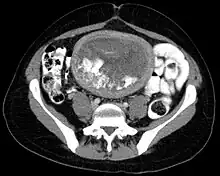

Hydatidiform mole on CT, axial view -